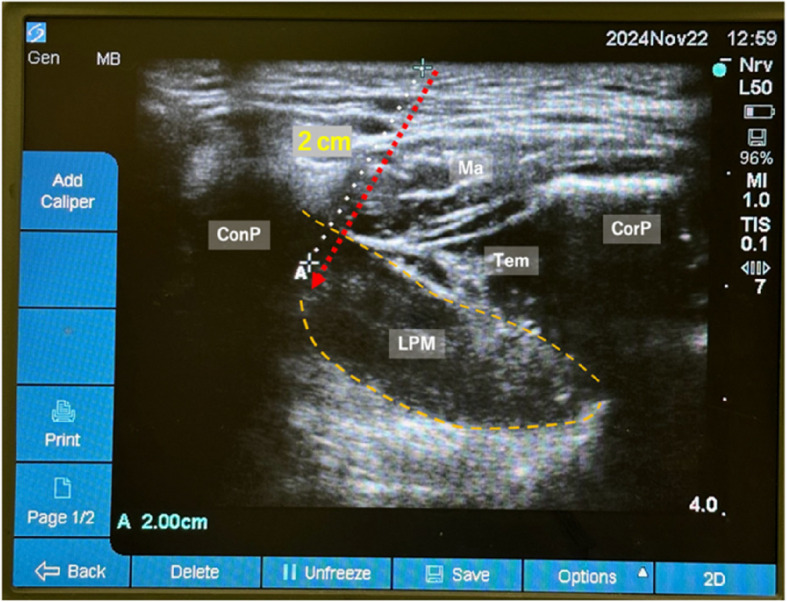

Background: Sagittal split ramus osteotomy is often associated with significant postoperative pain. Intraoral inferior alveolar nerve blocks have variable success rates and higher risks of vascular complications, while ultrasound-guided approaches to the pterygomandibular space require precise needle placement in a narrow anatomical space. We present a novel perioperative application of ultrasound-guided lateral pterygoid muscle injection for regional anesthesia.

Case presentations: Three female patients underwent bilateral sagittal split ramus osteotomy under general anesthesia. After anesthesia induction, ultrasound-guided lateral pterygoid muscle injections were performed using 10 mL of 0.25% levobupivacaine. All patients demonstrated excellent postoperative pain control (numerical rating scale score ≤ 2) with minimal analgesic requirements and no complications.

Conclusion: This novel lateral pterygoid muscle injection technique for perioperative analgesia demonstrates promising clinical efficacy through a simplified ultrasound-guided approach, providing effective opioid-free postoperative pain management for sagittal split ramus osteotomy.